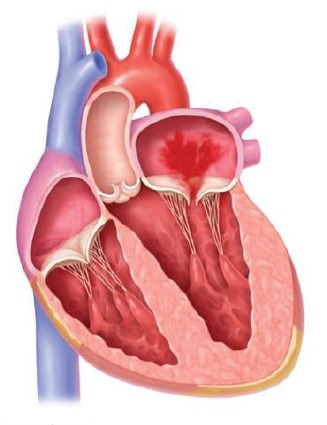

心臓は主に4つの部屋に分かれています。それぞれの部屋には、血液が逆流しないように、合計4つの扉(弁)がついています。肺で酸素化された血液は、まず左心房に集められ、次に全身へ血液を送り出すポンプ=左心室に充填されます。これら左心房、左心室の間に存在するのが、僧帽弁です。僧帽弁逆流症の多くは、弁と左心室の間を結ぶひも(腱索)が一部切れたり、左心室自体が大きくなることで弁がひっぱられたり、僧帽弁のわくが拡大することで、うまく弁が閉じることができなくなり、血液が左心室から左心房へ逆流してしまうことで生じます。

僧帽弁閉鎖不全症の僧帽弁

僧帽弁の左心室側にある腱索(僧帽弁と左心室を結ぶひも)が何らかの原因で切れたり、伸びたりすることで、僧帽弁自体の合わさりが悪くなり(接合不全)、血液が左心房へ逆流する状態です。

心筋梗塞などの虚血性心臓病、拡張型心筋症などにより左心室の動きが悪くなったり、心臓自体が拡大することで、僧帽弁を結ぶひも(腱索)がひっぱられたり、僧帽弁のわくが大きくなることで、僧帽弁自体の合わさりが悪くなり(接合不全)、血液が左心房へ逆流する状態です。